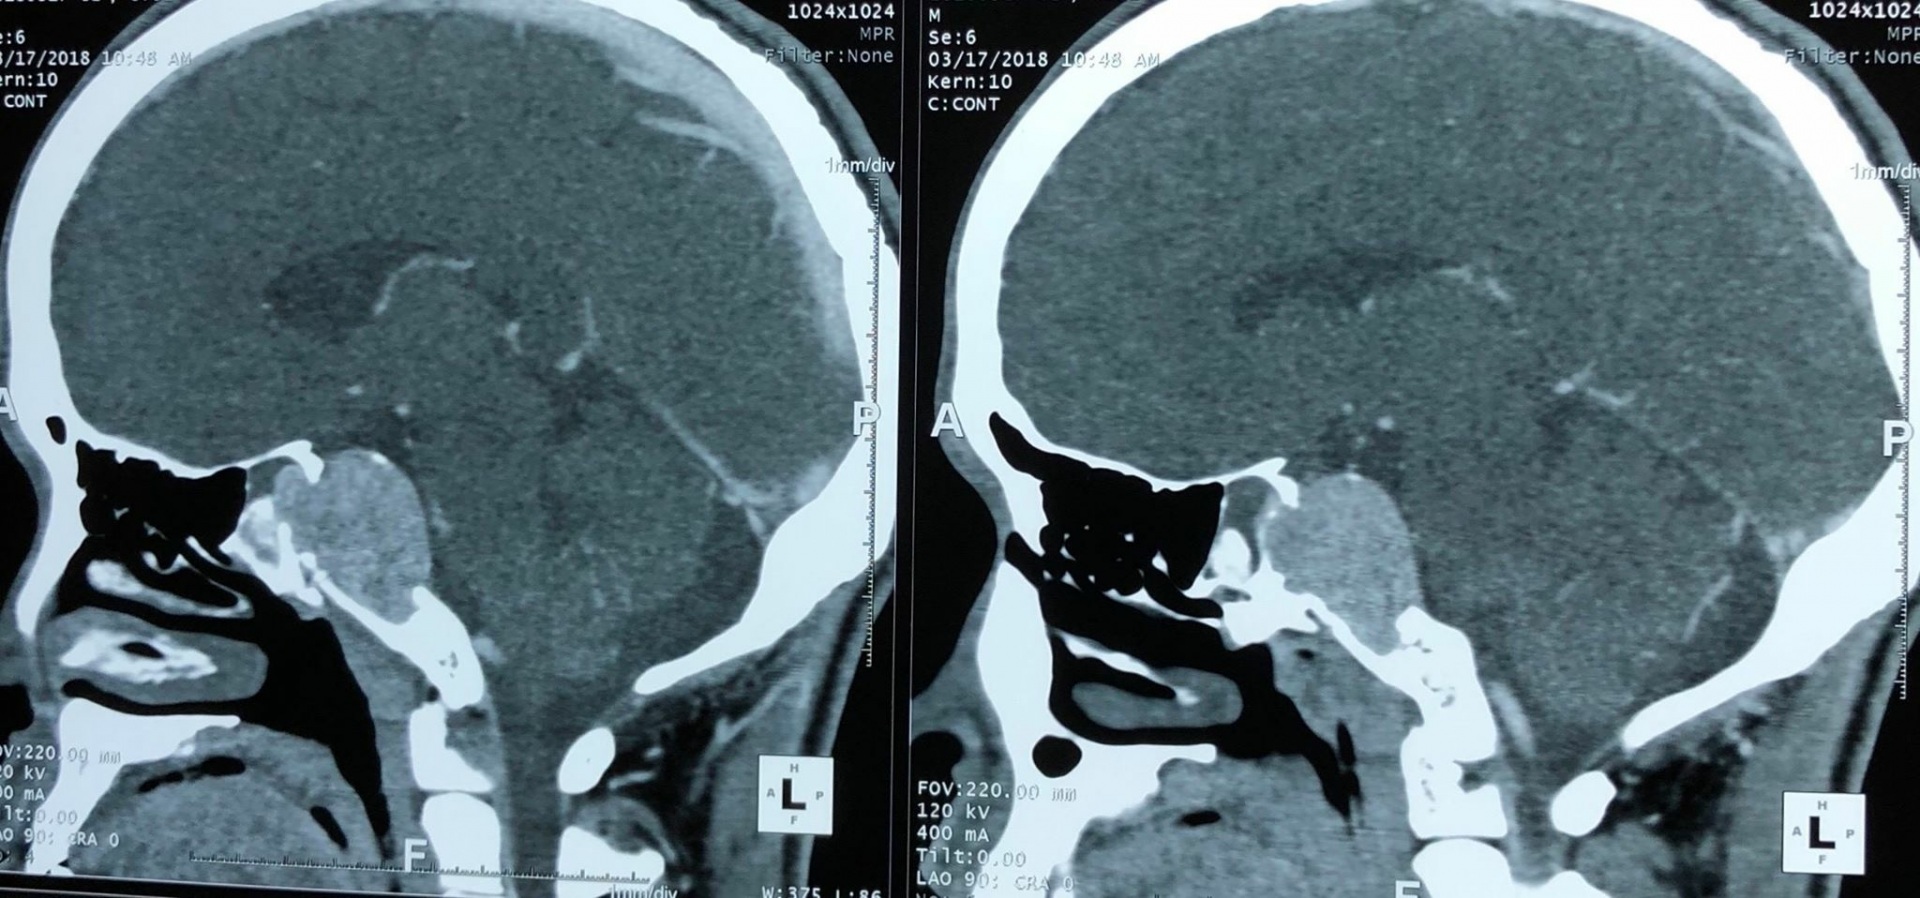

Đến khi không thấy có dấu hiệu thuyên giảm, bệnh nhân có biểu hiện đau đầu thường xuyên hơn thì mới nhập viện. Sau khi khám, chụp cộng hưởng và làm các chỉ định tại bệnh viện K, kết quả cho thấy có khối u não nền sọ vùng dốc nền có kích thước lớn 3 x 4cm.

| Hình ảnh phim chụp khối u trong nền sọ |